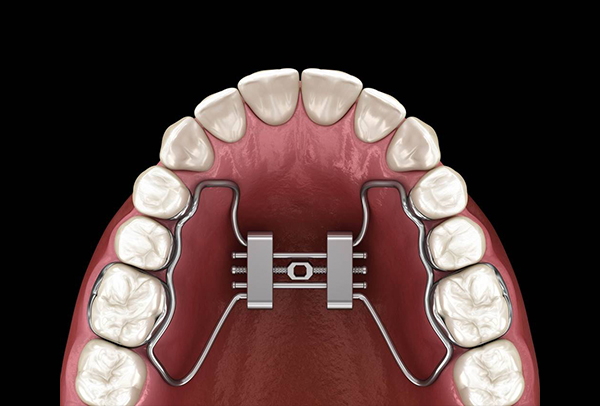

FA MARS 快速擴弓

「FA-MARS 固定式快速上顎擴弓系統」

是一種透過固定在上顎牙齒或顎骨上的矯正裝置,利用螺旋擴弓器逐步加壓,達到在短期內擴張上顎牙弓(特別是顎中縫)的治療方式。

應用在:上顎牙弓過窄、咬合不正(例如交叉咬合)、鼻腔氣道不足(改善呼吸)